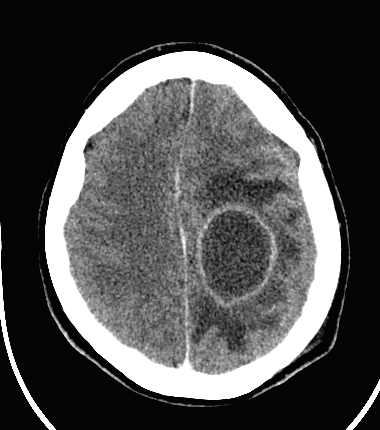

CT can usually lead to definitive diagnosis regarding brain tumors. A non-territorial localization (as opposed to arterial occlusion) of a usually “glove” shaped perifocal hypodense zone is highly suspicious for a tumor.

MRI has the greatest sensitivity in the detection of neoplastic brain lesions. The relaxation time of tumor is usually longer than that of the surrounding normal tissues. Therefore on T1W images neoplasms have slightly weaker signal intensity, while on T2W images they are more hyperintense than normal parenchyma. This signal pattern can be very characteristic and has great diagnostic value. However, secondary neoplastic signs, such as mass-effect of the tumor cannot be neglect either. A space occupying lesion can cause:

In higher grade astrocytomas there is a very typical, extensive perifocal swelling (finger-in-glove white-matter edema).

Contrast enhancement is usually round or it resembles a garland shape.

Small metastases can produce very extensive edemas. Multiplicity is common. Due to the consequential blood-brain barrier disorders their contrast enhancement is very intense.